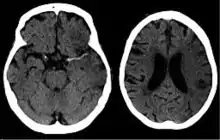

For diagnosing ischemic (blockage) stroke in the emergency setting:[63]

- CT scans (without contrast enhancements)

- sensitivity= 16% (less than 10% within first 3 hours of symptom onset)

- specificity= 96%

- MRI scan

- sensitivity= 83%

- specificity= 98%

For diagnosing hemorrhagic stroke in the emergency setting:

- sensitivity= 89%

- specificity= 100%

- sensitivity= 81%

For detecting chronic hemorrhages, MRI scan is more sensitive.[64]

CT scans may not detect an ischemic stroke, especially if it is small, of recent onset, or in the brainstem or cerebellum areas. A CT scan is more to rule out certain stroke mimics and detect bleeding.[9]